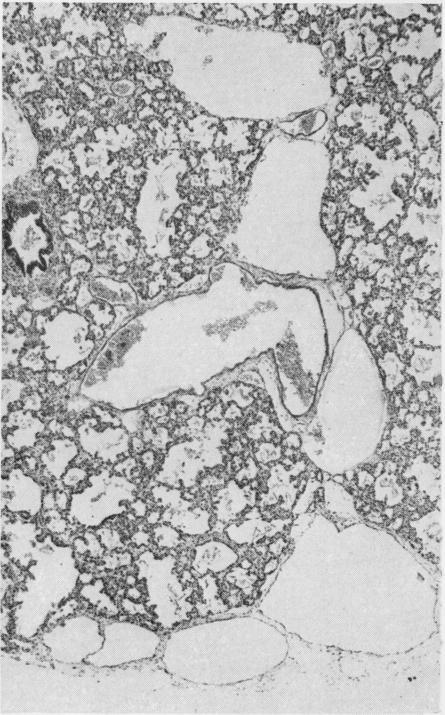

Congenital pulmonary lymphangiectasis.

J Clin Pathol. 1959 Jan;12(1):62-9. doi: 10.1136/jcp.12.1.62.